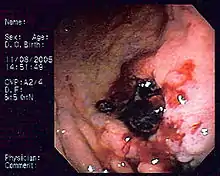

| Endoscopic image of gastric MALT lymphoma taken in body of stomach in patient who presented with upper GI hemorrhage. Appearance is similar to gastric ulcer with adherent clot. | |